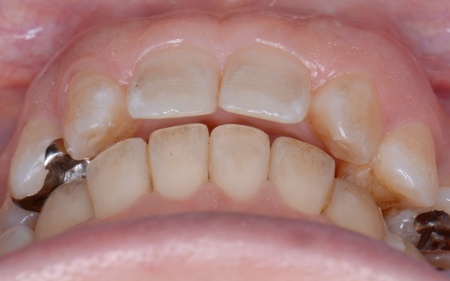

50代女性 インプラント・矯正・被せ物治療で見た目と噛み合わせを改善した症例

「以前治療した左下奥歯が思うように噛めない。また、矯正治療を受けた前歯でうまく噛めない」とご相談いただきました。

拝見したところ、左下奥歯(第1大臼歯)は以前、歯根分割処置が行われていました。

さらに患者様は全体的に歯並びや噛み合わせに問題があり、特に上下の前歯は噛んだ際に隙間ができ食べ物を噛み切りにくい状態です。

また、右の上下奥歯2本に装着されている白い被せ物や銀歯が劣化により歯に合わなくなり、虫歯の再発リスクが高まっていました。